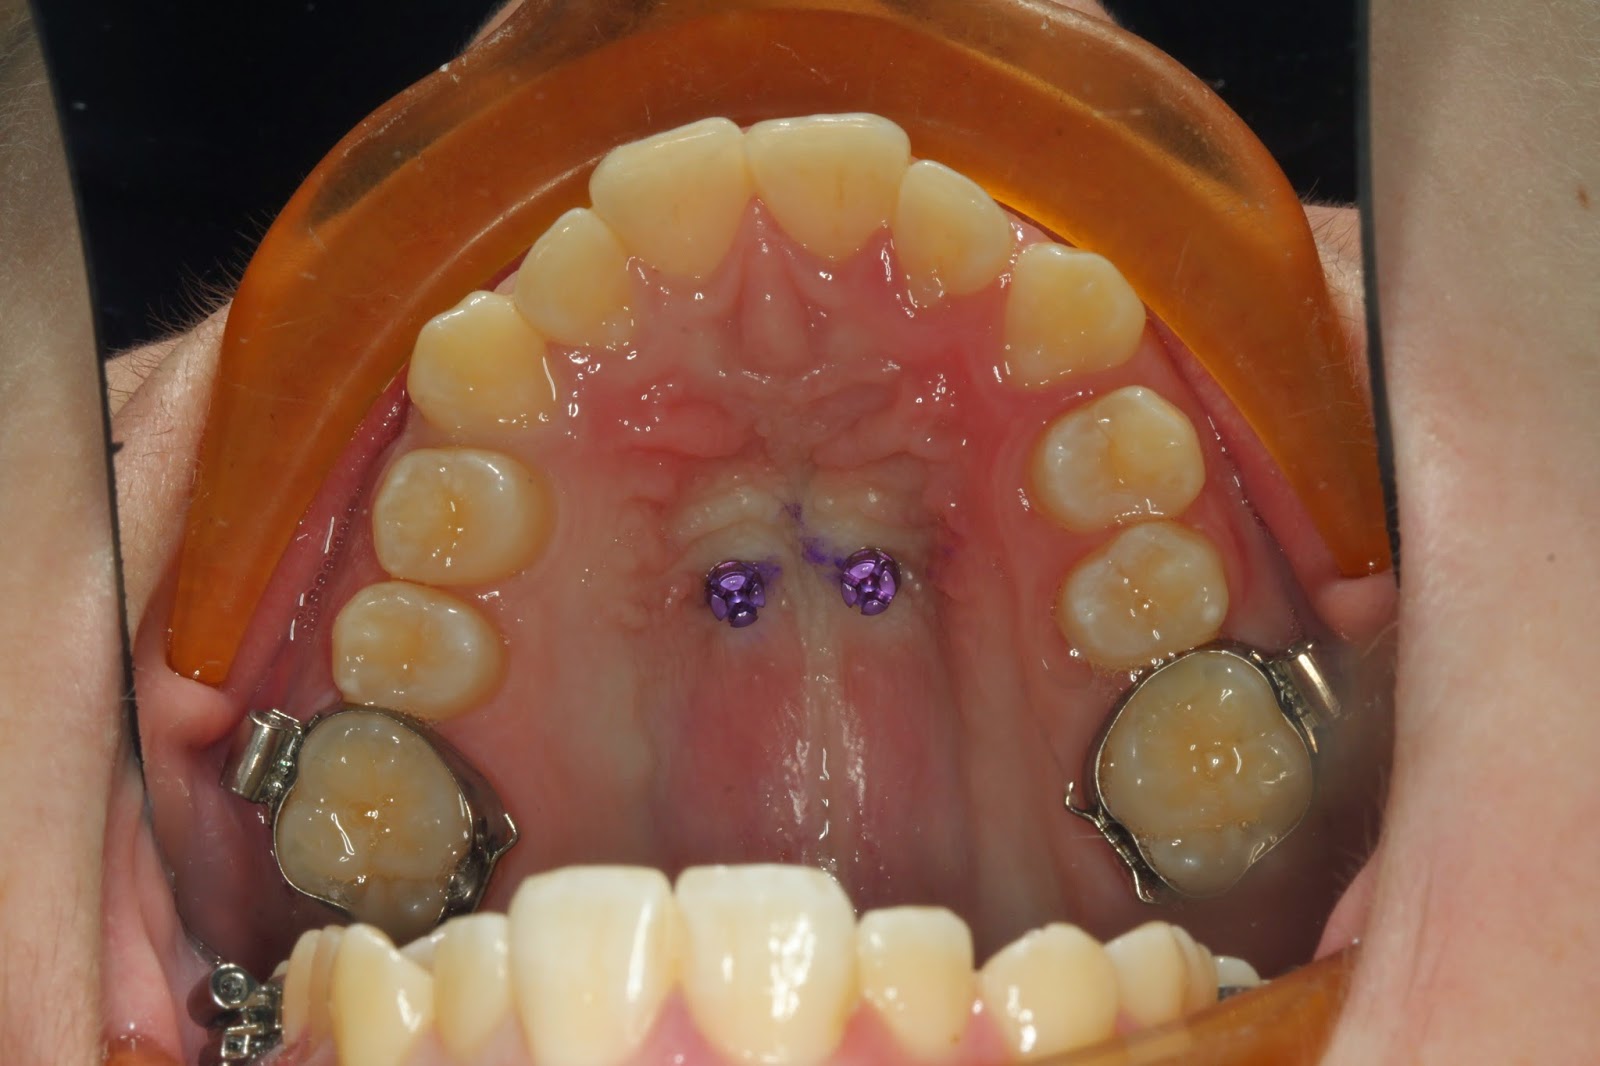

Benefit Palatal TADs ORTHOMAX Australia What Is A Tad In Orthodontics in orthodontics, a temporary anchorage device (tad) is one that is placed on the bone for a limited amount of time in. temporary anchorage devices (tads) serve as anchors to facilitate specific tooth movements in orthodontic treatment. the introduction of skeletal anchorage in the form of temporary anchorage devices (tads) or miniscrews has greatly. as a. What Is A Tad In Orthodontics.

From www.orthomax.com.au